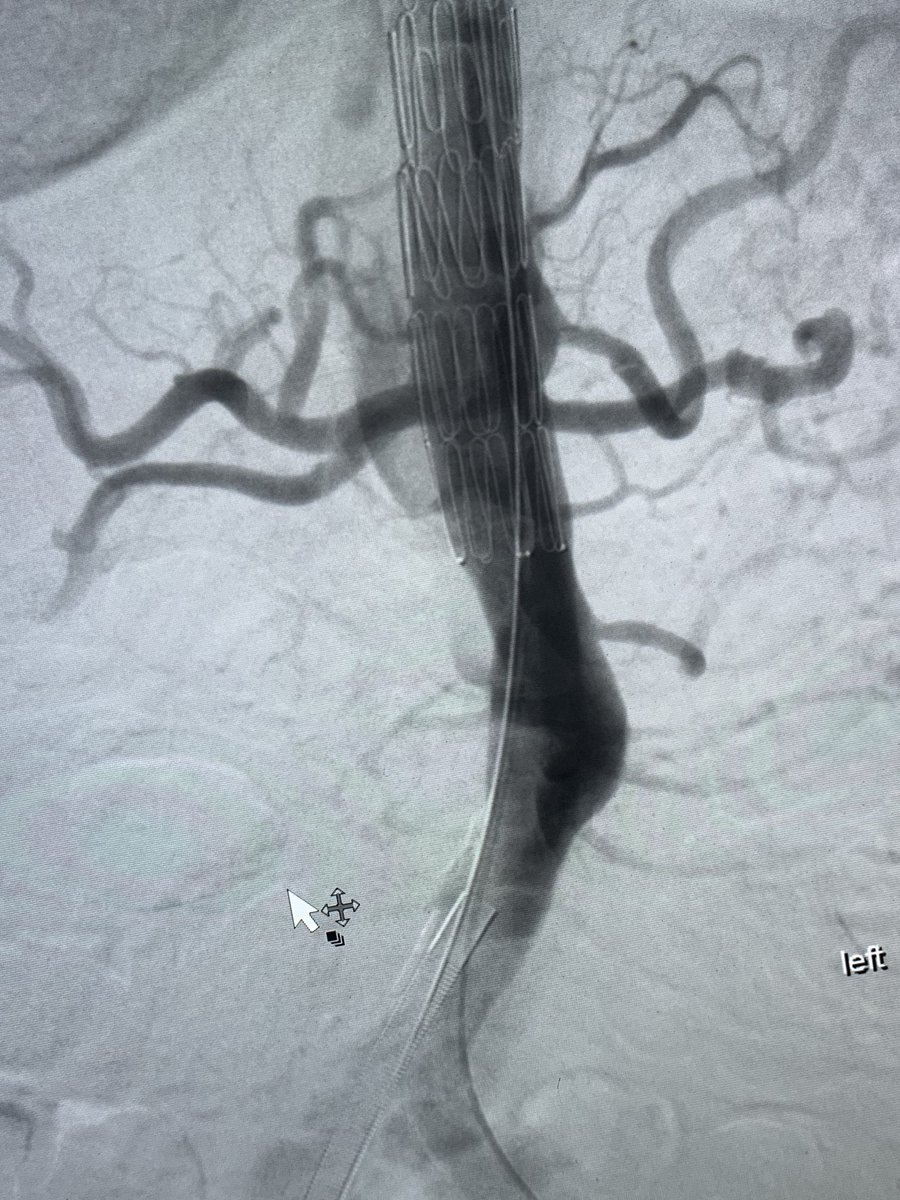

Central venous occlusion secondary to mesothelioma in a young patient with symptoms. R basilic, R CFV and RIJ access with the @InariMedical #ClotTrieverBOLD @anastasiah04 @CAIRweb